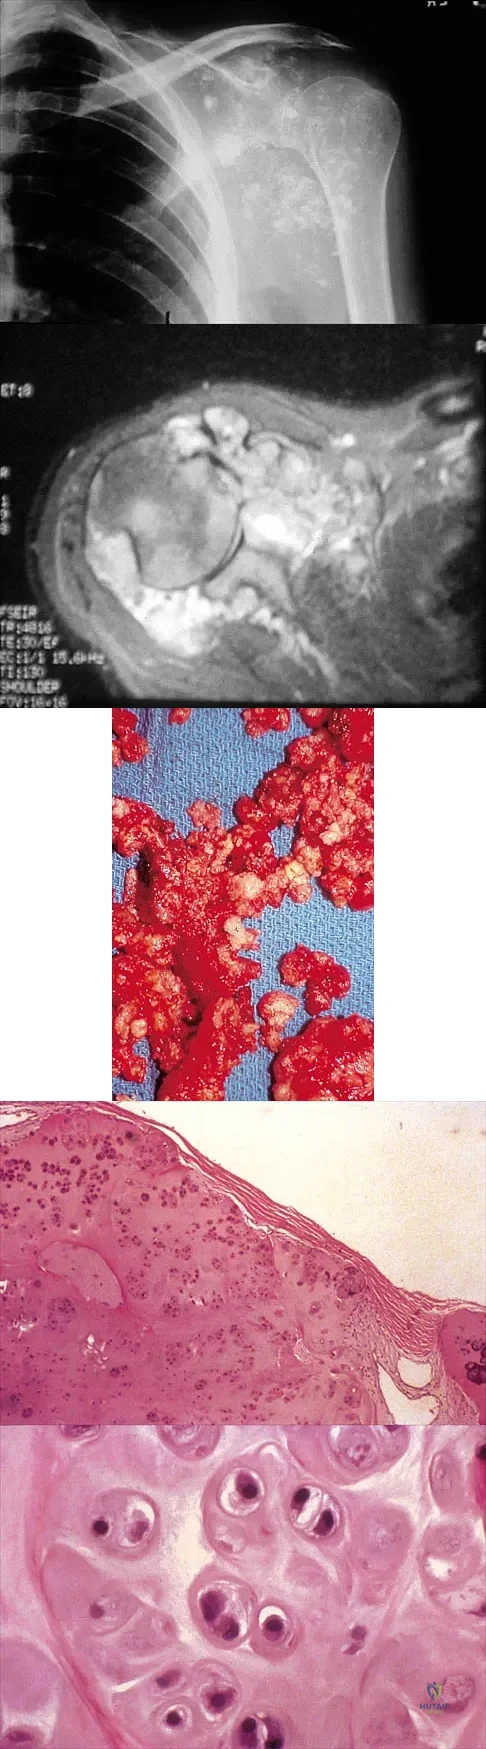

Question 38

A 32-year-old woman has had pain and a visibly growing mass in the shoulder for 3 years but denies any history of trauma. Examination reveals a swollen, boggy shoulder mass. The AP radiograph and MRI scan are shown in Figures 20a and 20b. Figures 20c through 20e show a portion of the excised mass and the photomicrographs of the biopsy specimen. What is the most likely diagnosis?

Explanation